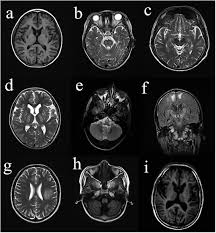

6 8 Neurologic WD is one of the main forms of the disease. In Wilson disease WD T2T2weighted T2w MRI frequently shows hypointensity in the basal ganglia that is suggestive of paramagnetic deposits. It is currently unknown whether this hypointensity is related to copper or iron deposition.

Interval changes on follow-up MR imaging were also closely correlated with clinical findings and. MRI of the brain appears to be more sensitive than CT scanning in detecting early lesions of Wilson disease. The face of the giant panda sign panda sign of the midbrain or double-panda sign is a characteristic pandas face appearance in magnetic resonance imaging MRI images of people with Wilsons disease.

1 In addition a second miniature panda face can be seen in the high signal abnormality in the pons figure C. To describe the spectrum of brain abnormalities in Wilson disease hepatolenticular degeneration as depicted at magnetic resonance MR imaging and computed tomography CT and to relate these findings to neurologic and hepatologic abnormalities.

To describe the spectrum of brain abnormalities in Wilson disease hepatolenticular degeneration as depicted at magnetic resonance MR imaging and computed tomography CT and to relate these findings to neurologic and hepatologic abnormalities. Positive findings believed secondary to this condition were found in 15 subjects. It is found worldwide with a prevalence of approximately 1 case in 30000 live births in most populations. Thirty-eight patients with biochemically proven Wilsons disease underwent magnetic resonanceimaging MRI of the brain as well as neurological examinations. Fifty patients with Wilson disease participated in the cross-sectional. The face of the giant panda sign panda sign of the midbrain or double-panda sign is a characteristic pandas face appearance in magnetic resonance imaging MRI images of people with Wilsons disease. 1 In addition a second miniature panda face can be seen in the high signal abnormality in the pons figure C.